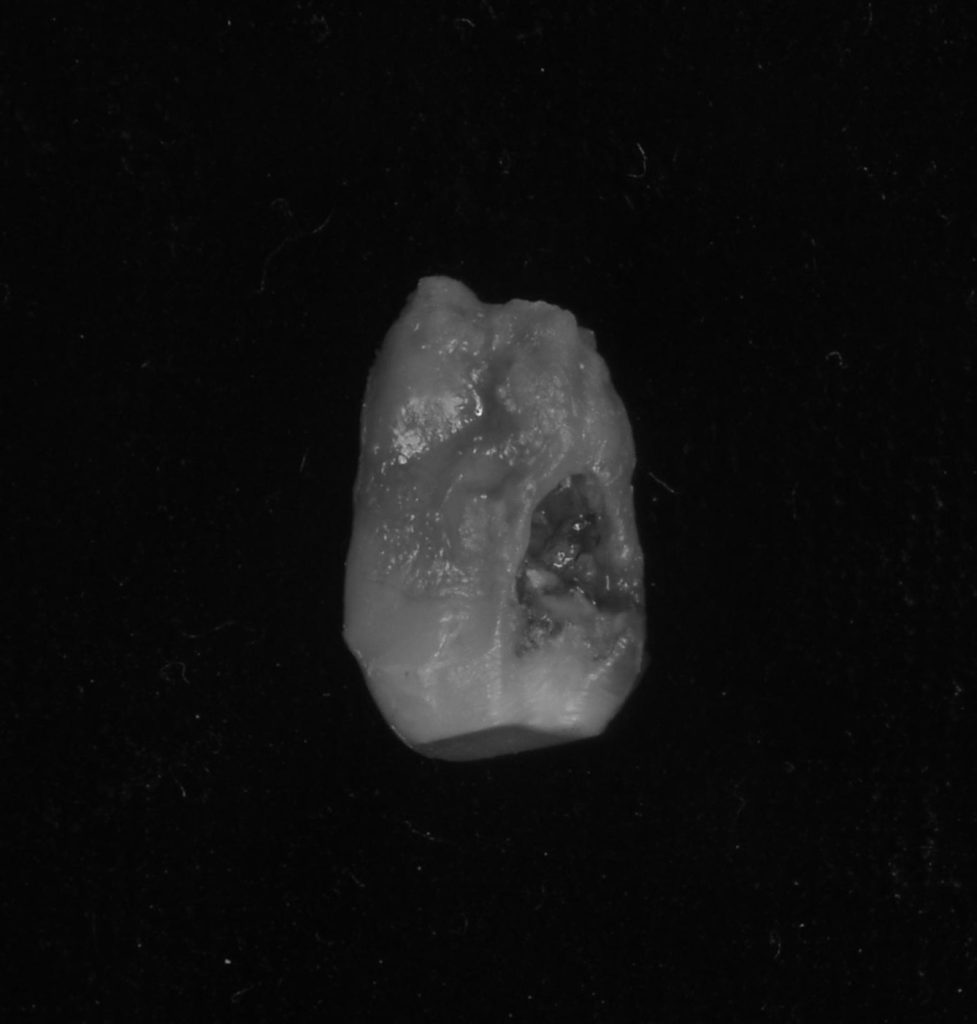

神経が無く、症状を感じにくい状態ですが、歯根内部に吸収があり、いわゆる穴が空いていました。(専門的には外部吸収と言います)